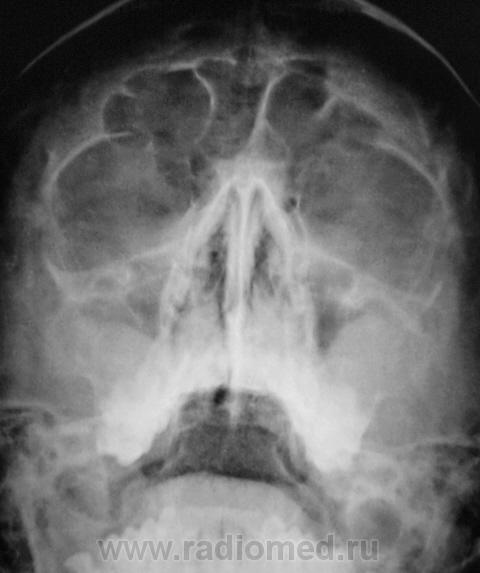

Пациент направлен оториноларингологом на рентгенографию придаточных полостей носа.

Произведено стандартное исследование.

В центральной ячейке лобной пазухи - уровень жидкости - фронтит. в верхнечелюстных пазухах - картна кист, и сфеноидит...

Ячейки решетчатых костей с обеих сторон затемнены, имеются пристеночные теневые наслоения в обеих в/челюстных пазухах, больше у наружных стенок, , с четкими выпуклыми контурами, носовые ходы сужены. R-картина синуита. В наличии горизонтальных уровней в лобных пазухах сомневаюсь. А что бы определиться с основной пазухой, хорошо бы сделать боковую проекцию.

То же склонен видеть уровень жидкости в лобных (видно что повторяет наклон), пристеночное подушкообразное утолщение слизистой в верхнечелюстных, сфеноидит.

Согласна с коллегой по поводу сомнительности затемнения лобных пазух, это может быть обусловлено ячейками решетчатой кости.